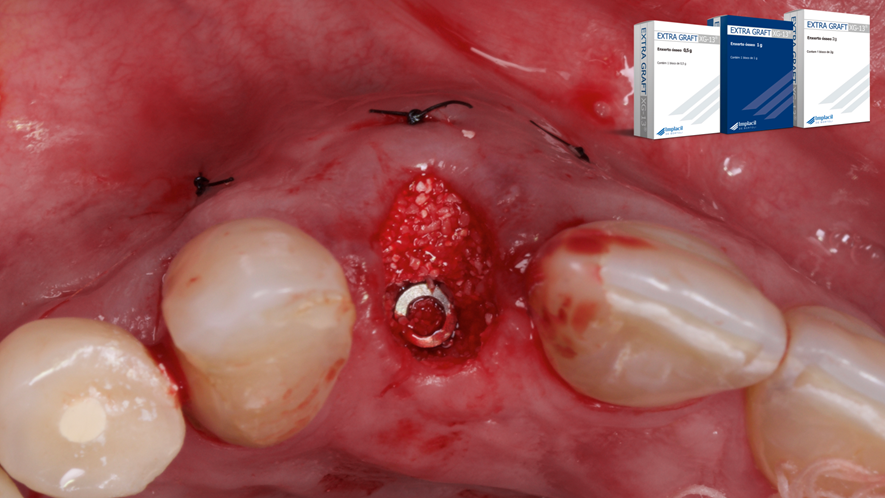

Este trabalho tem como objetivo relatar um caso clínico de exodontia minimamente invasiva de um incisivo lateral superior com fratura radicular, realizando implante imediato em alvéolo pós-extração, enxerto de tecido conjuntivo subepitelial e osso bovino liofilizado para preenchimento de GAP, prontamente à instalação de pilar reto e provisório imediato.